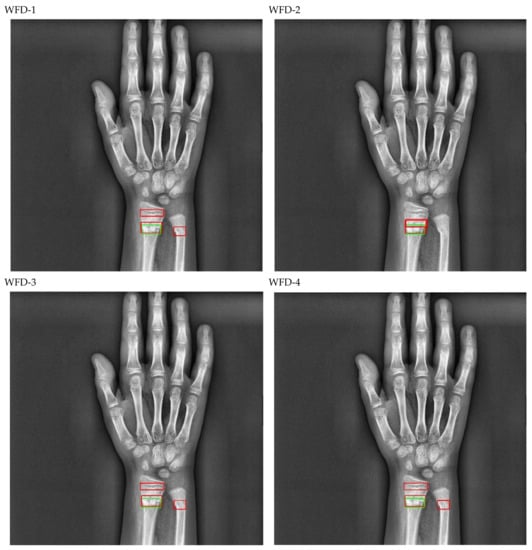

The bounding box outputs achieved from fracture detection performed with ensemble models in wrist X-ray images are provided in Figure 20 and Figure 21 below as a sample for the right/left hand in the dataset.

Figure 20.

Sample of right wrist fracture results [ground-truth bounding box (green), predicted bounding box (red)].

Figure 21.

Sample of left wrist fracture results [ground-truth bounding box (green), predicted bounding box (red)].

The predicted bounding boxes achieved fracture detection suggest that, as shown in the images in Figure 20 and Figure 21, the model that provides the most accurate results that are closest to the ground-truth bounding boxes is the WFD-C ensemble model developed in this study. Moreover, the examination of the number of predicted bounding boxes reveal that the model with the lowest number on the test data is also WFD-C. For the fracture detection in wrist X-ray images, Figure 22 below shows the total number of predicted bounding boxes obtained for each model on the test dataset as the result of the fracture detection performed with a total of 26 deep learning models, six of which are ensemble models.